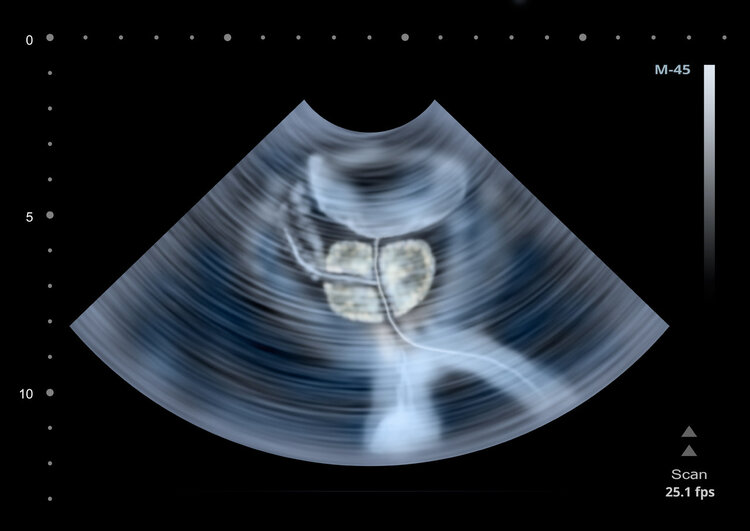

2.前列腺疾病

前列腺被称为男人的“生命腺”,由于对前列腺缺乏认知或生活习惯不良等,50岁前是男性前列腺炎的高峰期,尤其是青壮年时期的男性,由于性功能旺盛,不断刺激前列腺,容易引发前列腺炎。前列腺炎的典型症状之一就是私处潮湿,同时伴随着排尿不适、下体疼痛、功能障碍等症状。